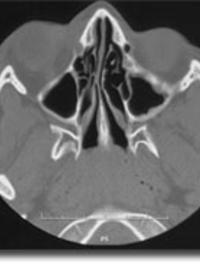

Sept [...]